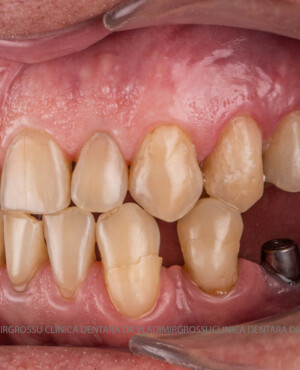

Protezarea pe implanturi dentare este soluția modernă, estetică și funcțională pentru înlocuirea dinților lipsă. Această procedură combină precizia chirurgicală cu tehnologia avansată de laborator pentru a reda pacienților zâmbetul natural, vorbirea clară și capacitatea de a mânca fără restricții.

La Clinica Dentară Dr. Grossu din Chișinău, oferim protezări pe implanturi dentare personalizate, realizate de o echipă multidisciplinară, cu ajutorul celor mai noi tehnologii digitale și materiale biocompatibile.

- Estetică superioară – imită perfect dinții naturali